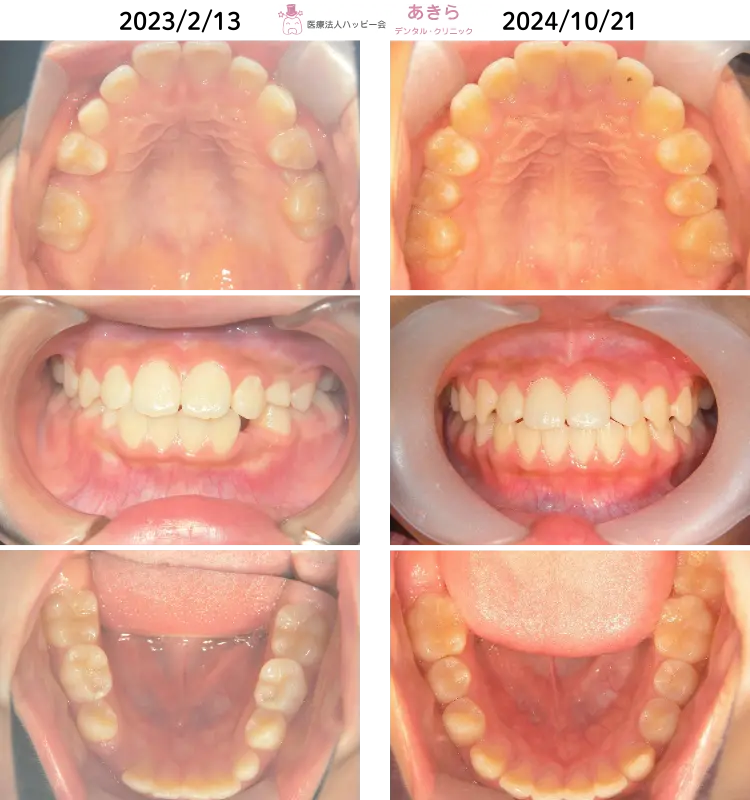

2023年2月13日 初診 ⇒ 2024年10月21日 経過時

経過

- 上下左右7番の咬合を確認して「SH療法」を終了予定です。

回数

20回

後に経過資料採得をして『SH療法』終了予定。

治療期間

1年7ヶ月